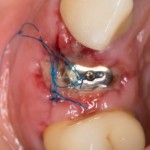

Швы мы сняли через 10 дней, а через две недели послеоперационная рана выглядит следующим образом:

Да, с гигиеной есть небольшая проблема, на формирователе зубной налет. Но это потому, что я сказал пациентке ничего не трогать — и она строго выполняла все рекомендации. Я поменял формирователь на новый, проверил эпителизацию краев раны, после чего направил пациентку к своему коллеге и другу Ахинян Давиду.

Он фиксирует на имплантат временную коронку:

Она изготавливается из композитной пластмассы на абатменте XiVE TempBase, который, кстати, входит в комплект поставки вместе с имплантом. Согласитесь, это очень удобно.

Коронка фиксируется винтом. Мы оставляем ее до момента интеграции импланта (несколько месяцев), плюс еще немного времени.